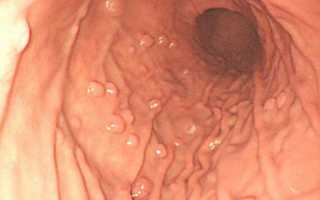

Гиперпластический полип желудка — это образование из эпителиальных клеток, как правило, до 2 см. Однако не исключен их рост до больших размеров. Образование часто имеет ножку, то есть сужение у основания. Сам по себе гиперпластический тип не способен озлокачиваться, но может привести к раку окружающих тканей. Это называется метаплазией эпителия, то есть изменением его клеток.

Формироваться гиперпластические полипы могут практически по всему органу: антральной, кардиальной, фундальной области. Наиболее частое (около 70%) место локализации — поворот желудка, то есть пилорический отдел.

Этот вид образований иногда классифицируют отдельно наравне с аденоматозным и гиперпластическим, но чаще относят к последнему. Гиперплазия — это быстрый рост, формирование, увеличение числа клеток ткани. Поэтому гиперплазиогенные полипы характеризуются стремительным разрастанием. По внешнему виду их сравнивают с цветной капустой. За счет своей гиперспособности к делению клеток такие наросты подвержены риску перерождения в раковую опухоль. Поэтому научная медицина относит гиперплазиогенный полип к предраковому состоянию.